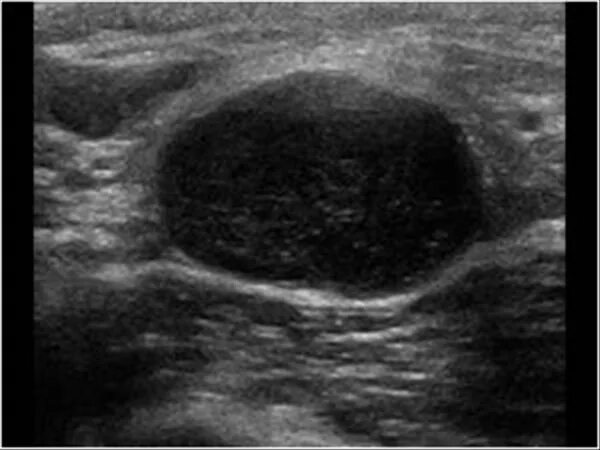

Лимфоузел в паху слева у мужчины